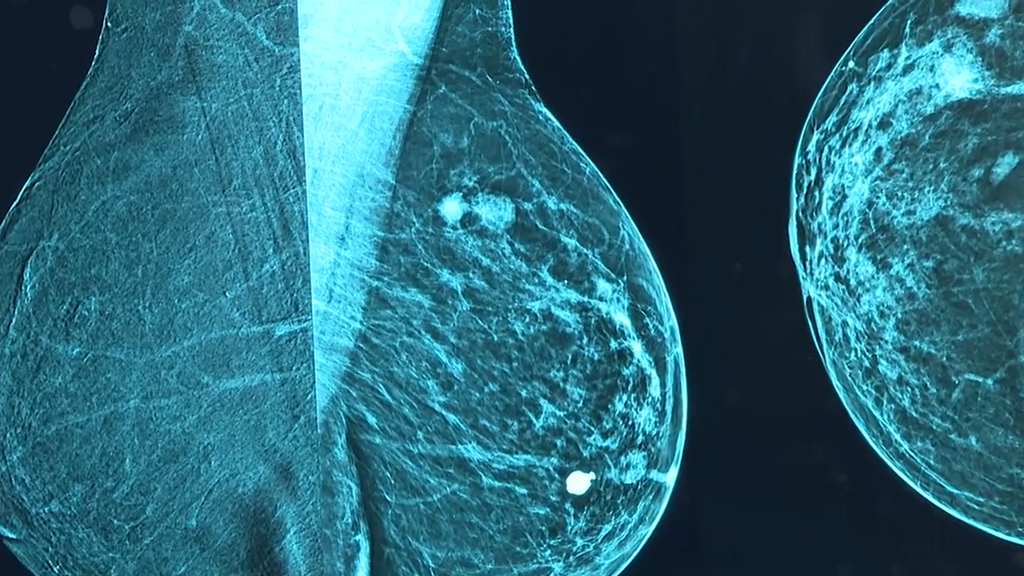

La crisis de los cribados del cáncer de mama en Andalucía sigue sin respuestas claras, aunque la ministra de Sanidad, Mónica García, ha reafirmado su compromiso de llegar hasta el final para esclarecer qué ha fallado y evitar que se repitan situaciones similares. Tras reunirse con la asociación AMAMA, que agrupa a las afectadas, la ministra insiste en que el Ministerio utilizará todas las vías posibles, judicial, administrativa o civil, para esclarecer el caso.

Durante el encuentro, García reconoce que el problema de los cribados afecta a todo el sistema, pero subraya que la situación en Andalucía ha revelado una grave falta de control y coordinación. También acusa a la Junta de Andalucía de haber privatizado partes del procedimiento de revisión de mamografías, lo que afectó a la calidad del programa.